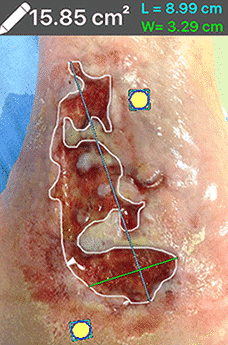

The device, MolecuLight i:X is used in a darkened room while it illuminates the wound using its special blacklight, while other images can be acquired with the room lights on. The device can then help generate outlines of the wound and provide automatic area measurements. Additionally, it can help guide where to swab the wound to best sample it for bacteria.